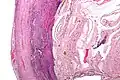

Pathology

Even for clinically certain appendicitis, routine histopathology examination of appendectomy specimens is of value for identifying unsuspected pathologies requiring further postoperative management.[58] Notably, appendix cancer is found incidentally in about 1% of appendectomy specimens.[59]

Pathology diagnosis of appendicitis can be made by detecting a neutrophilic infiltrate of the muscularis propria.

Periappendicitis, inflammation of tissues around the appendix, is often found in conjunction with other abdominal pathology.[60]

Micrograph of appendicitis and periappendicitis. H&E stain.